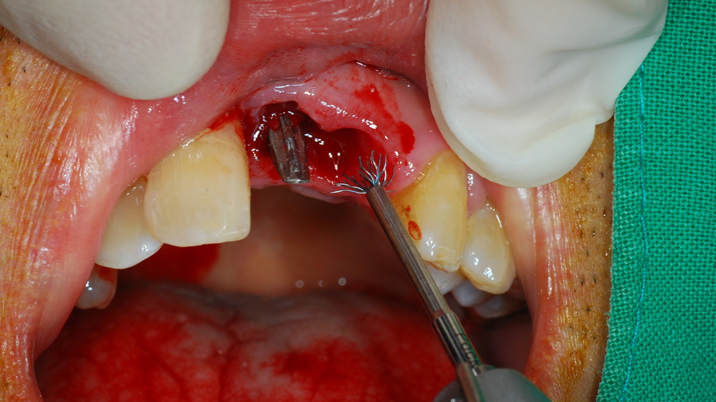

“Achieving a clean surface is the key to treating peri-implantitis!Using a titanium or NiTi brush for the decontamination process along with proper GBR can successfully restore the peri-implant environment. ”

Clinical case: Peri-implantitis treatment case using titanium or NiTi brush

- Courtesy of Dr. Dae-Hee Lee, South Korea -

Dr. Dae-Hee Lee,Maxillary Anterior,Peri-implantitis,Bone regeneration,Aesthetic zone,#21,#22,GBR,Titanium Brush Set

Titanium Brush Set